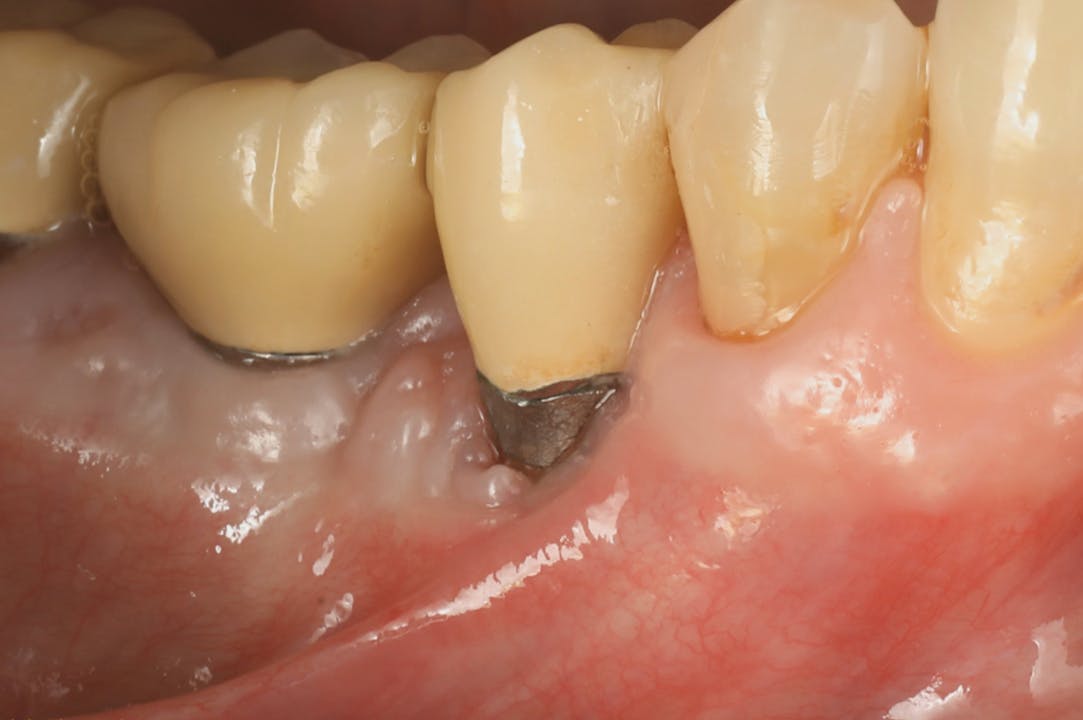

CLINICAL VIDEO Post and Core Restoration Replacement of missing tooth Gide Dental Reviews Premiere provider of online dental education. Evidence based video education at its best. Learn from the world's most trusted faculty and advance your skills with gide. Read 26 customer reviews of gide dental center, one of the best. Clinical videos, expert interviews, live broadcasts over. Gide dental | 280 followers on linkedin. • 550+ clinical videos on web and app. Gide Dental Reviews.